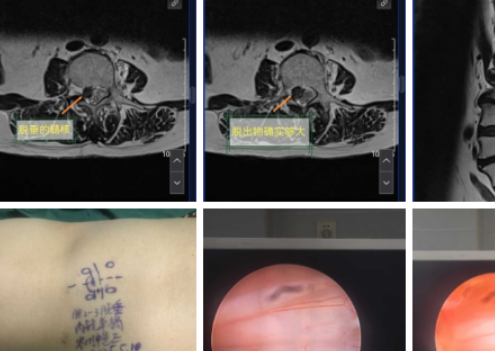

UBE surgery - thoracic decompression - AYDEFY

Lumbar UBE Minimally Invasive SurgeryHemostasis Technology